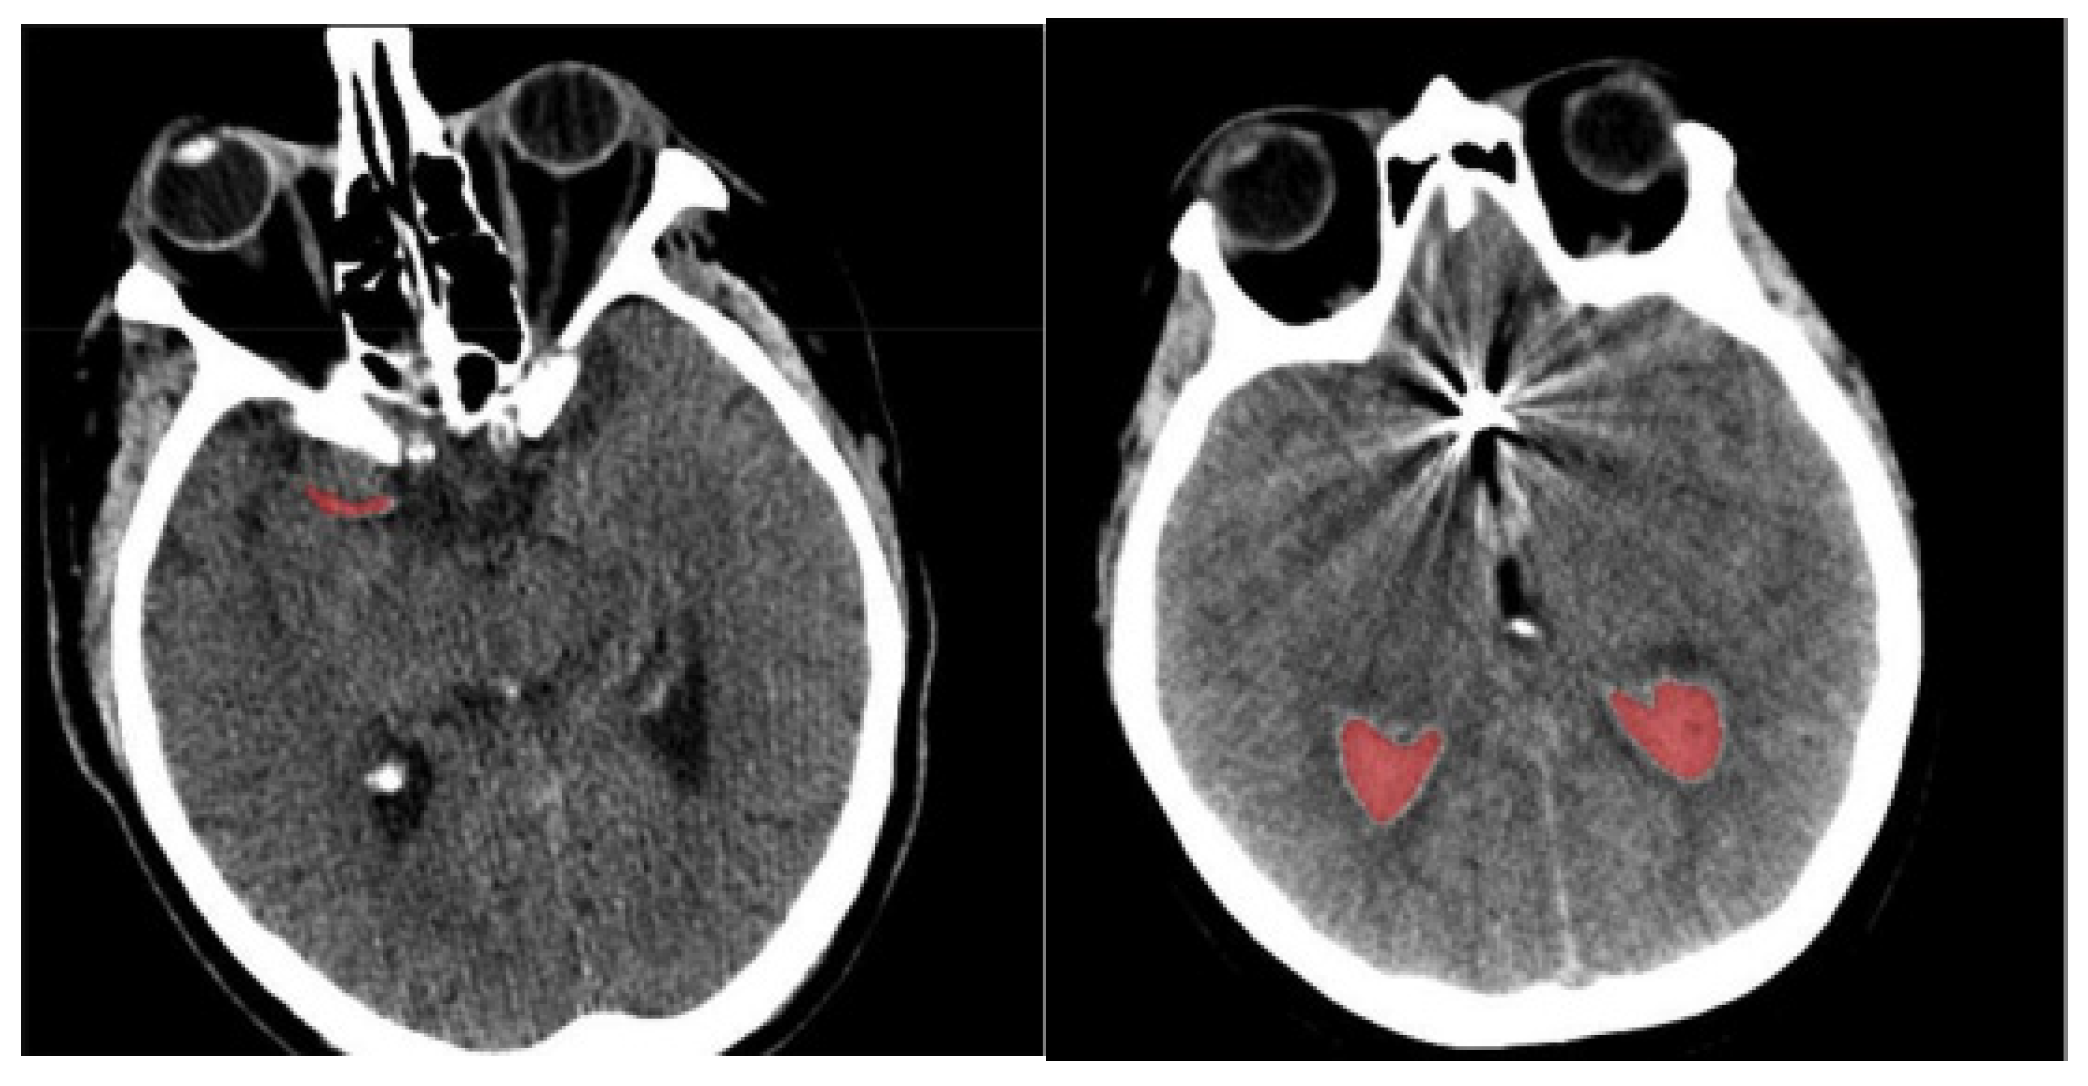

- Finally, determine the differences in orientation and intensity of the pixels and using Equations (3) and (4). The sample-segmented images are graphically presented in Figure 3, where the red area denotes the segmented portions.

Figure 3. Sample-segmented images.

The process of segmentation using modified region-growing is important, because it mainly impacts the capacity of feature extraction and classification because the poor segmentation causes noise or irrelevant details which affect classification. A precise segmentation separated the hemorrhagic regions from the images and confirmed that only appropriate areas were transferred to feature extraction. This helped in extracting the significant features that lead to the enhancement of the capacity of classifying the SAH grade. After performing the segmentation, the isolated portions were given as input to the feature extraction where the pre-trained models were utilized to extract appropriate features.